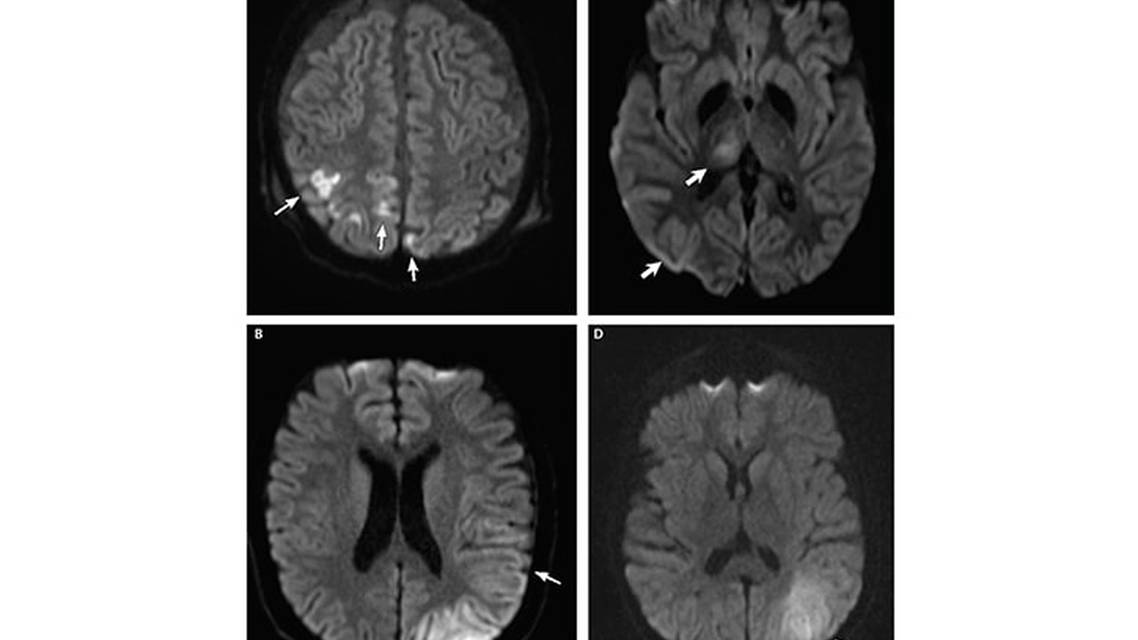

Disorders of Mitochondrial DNA. Metabolic encephalopathy, lactic acidosis and stroke-like episodes (MELAS) is the prototypical metabolic disorder that presents with acute metabolic stroke. In approximately 80% of cases, MELAS is caused by a missense variant of the MT-TL1 mitochondrial gene (m.A3243G). The remainder of cases are caused by other variants in MT-TL1 or in other mitochondrial genes.4 The mechanism of injury in MELAS is reversed from traditional arterial stroke; instead of poor blood flow causing brain injury, brain tissue involved in a metabolic stroke is stressed by increased metabolic demand (eg, febrile illness), and localized swelling secondarily restricts blood flow, resulting in further ischemic injury. As such, the SLE lesions seen in MELAS typically do not conform to a vascular territory.5 A primary diagnostic criterion for MELAS is the presence of SLE on MRI, because over 90% of people with MELAS will experience SLE during their lifetime (Figure 1). Seizures often occur in conjunction with SLE and may be difficult to control. As increased blood flow and electrical hypersynchrony escalate metabolic demand, further stressing and extending the injured area, seizure activity can spread and persist in tissue along the penumbra.

Symmetric MRI findings include diffusion-restricted lesions that have a predilection for the basal ganglia, brainstem, and cerebellum (Figure 2). During acute illness, there are often new neurologic findings as well as progression of previous MRI abnormalities that can culminate in bilateral necrotic lesions of the deep gray nuclei. Of note, arterial spin labeling shows a counterintuitive hyperperfusion within lesions,17 perhaps signifying a state of increased metabolic demand more substantial than cytotoxic edema. During acute periods of neurologic injury, fluid support, metabolic support and treatment of underlying triggers is crucial. At present there are no mitochondrial-targeted therapies, and there remains no evidence for the use of arginine in the acute management of LS.

Glutaric Aciduria. A progressive autosomal recessive disorder, glutaric aciduria is characterized by macrocephaly with delayed development, punctuated by periods of severe metabolic decompensation resulting in hypotonia, encephalopathy, and seizures.18 The genetic deficiency is in glutaryl coenzyme A dehydrogenase< (GCDH), a mitochondrial matrix protein. Absence of GCDH causes a selective abnormality amino acid metabolism resulting in buildup of glutaric acid. Dietary management is crucial, including avoidance of lysine- and tryptophan-containing foods and supplementation with L-carnitine. For unclear reasons, the striatum is at particular risk and undergoes necrotic changes that are notable on MRI (Figure 2). Retrospective studies have suggested that the selective vulnerability of the striatum may be evident on imaging even before clinical symptoms are present.19